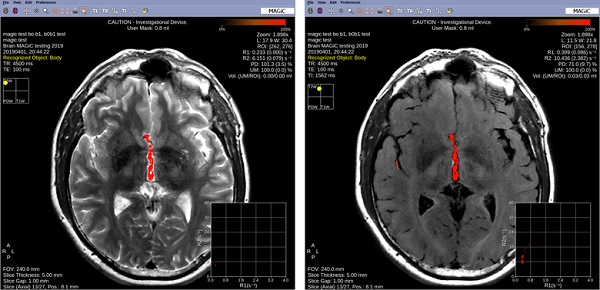

Figure 2. ROI around area to change

2. Right-click to open the right-click menu.

Figure 4. User mask on left and ROI to Null Tissue on right